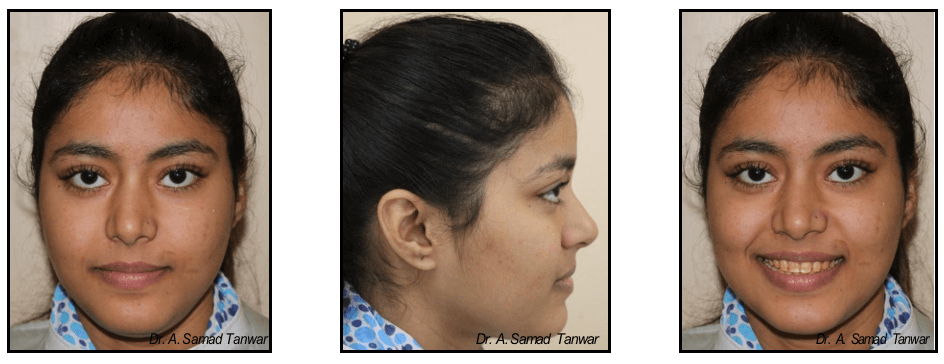

Patient reported to the Department of Prosthodontics with a chief complaint of discoloured teeth

The intraoral photographs of the patient reveals yellowish discolouration of teeth with generalized

On thorough clinical examination it was found that patient has enamel hypoplasia.